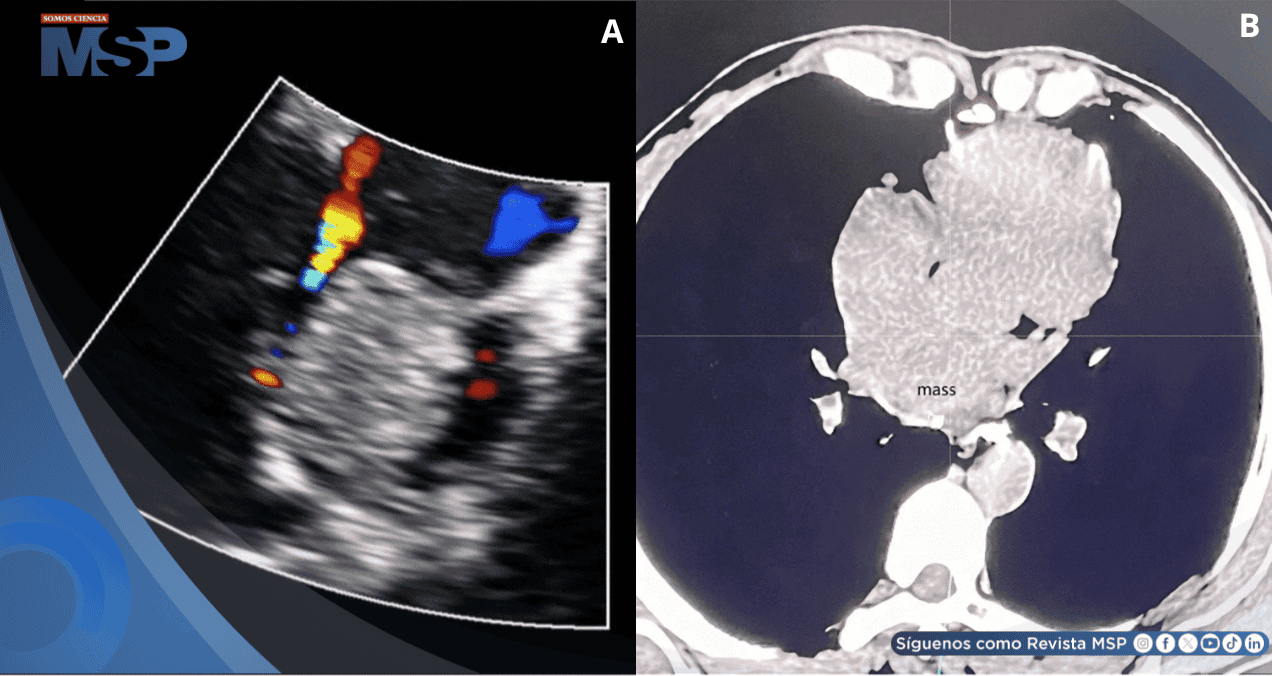

En el último ingreso se le realizó un electrocardiograma que mostró un ritmo sinusal, taquicardia nodal no paroxística y desconexión auriculoventricular incompleta. La ecocardiografía transtorácica reveló una masa ecogénica anómala de 5 cm × 4 cm en la aurícula izquierda, adherida a la parte media del tabique auricular.

La ocupación de la aurícula izquierda provocaba compresión de la vena cava superior, y la pared ventricular izquierda presentaba un engrosamiento uniforme de 15 mm. El diagnóstico inicial fue mixoma del tabique auricular, cuyo movimiento podría provocar la obstrucción de la circulación sanguínea, por lo que se recomendó la intervención quirúrgica.

Las herramientas de imagen cardiovascular multimodal, como la ecocardiografía, la tomografía computarizada y la resonancia magnética cardíaca, desempeñan un papel clave en la evaluación inicial. No obstante, su precisión puede verse limitada por las características del tumor y su localización anatómica.